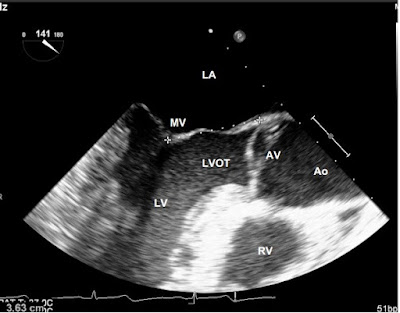

2.2.5. Mặt cắt trục dọc qua van động mạch chủ giữa TQ (Mid

Esophageal Aortic Valve long axis view):

* Cách tìm: Từ mặt cắt trục ngang qua van động mạch chủ giữa TQ, xoay mặt cắt

đa diện khoảng 120 -160 (90 từ mặt cắt trục ngang) đến khi xuất hiện đường ra

thất trái, van động mạch chủ và động mạch chủ lên.

* Các cấu trúc khảo sát được: Nhĩ trái (LA), van 2 lá (MV), thất trái (LV),

đường ra thất trái (LVOT), van động mạch chủ (AV), động mạch chủ lên (Ao), thất

phải (RV).

* Khảo sát Doppler: Dòng qua van động mạch chủ.